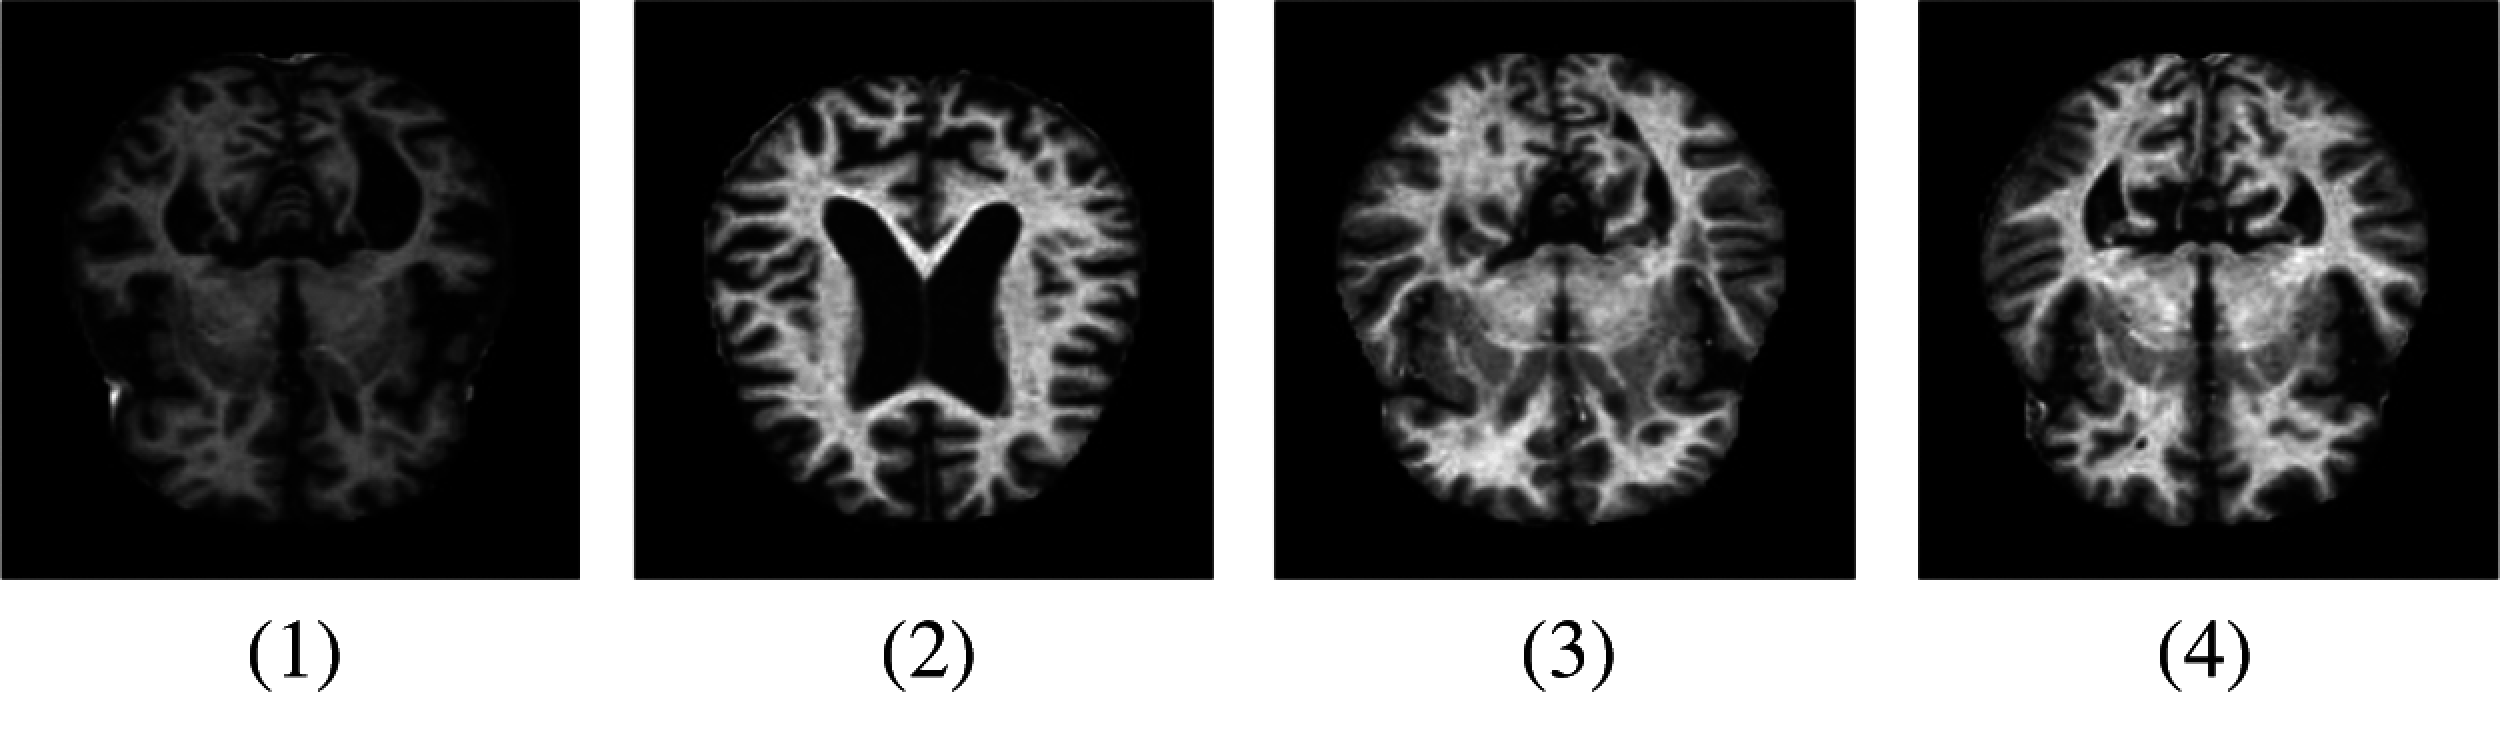

AlexNet is a pre-trained model in convolutional networks. Using a pre-trained model is known as transfer learning and this notion is frequently used in deep learning applications nowadays. The AlexNet algorithm is trained on a large number of datasets of ImageNet which were labeled images of more than 15 million [19]. We used a modified version of this AlexNet model in our proposed methodology. This network AlexNet is 8 layers deep with learnable parameters in which 5 layers are Convolutional layers with a combination of max pooling and 3 Fully Connected Layers. Each layer has a nonlinear activation function called ReLU. The input layer in the network reads images that came from the Pre-processed layer. Pre-processing of images is a necessary step to obtain proper datasets that can be done in many ways i.e., to enhance some Image features or image resizing. Image resizing is an essential step because images have different variated dimensions. Therefore, images were resized into 227 * 227 * 3 where 227 * 227 represents the height and width of the input images, and 3 demonstrates the number of channels. The MRI images representing different AD stages after Pre-processing are represented in Fig. 4.

Figure 4: Samples of MRI images after pre-processing. (1) MD; (2) MOD; (3) ND; (4) VMD